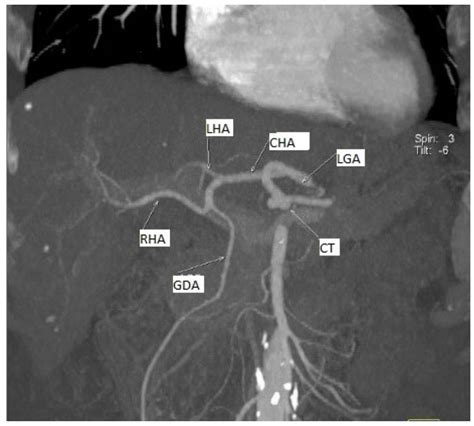

The Hepatic Artery Common arises from the celiac trunk, which is the first major branch of the abdominal aorta. From this origin, it travels a short distance before bifurcating into two major terminal branches: the proper hepatic artery and the gastroduodenal artery. Its placement is strategic, situated deep within the upper abdomen and behind the lesser omentum, making it a focal point during abdominal surgeries and interventional radiology procedures.

The intricate branching pattern of the vascular supply is often described through various anatomical classifications, such as the Michels classification system. While the “classic” presentation involves a direct path from the celiac trunk, anatomical variations are surprisingly common. Surgeons must be hyper-aware of these variations—such as a replaced or accessory hepatic artery—because damage to these structures during biliary or gastric surgery can lead to severe ischemic complications for the liver.

CT Angiography (CTA) Provides high-resolution mapping of the vessel and its branches.

In the modern medical landscape, the treatment of arterial disorders has shifted toward minimally invasive procedures. Stenting, angioplasty, and embolization are common interventions performed by radiologists. For instance, in patients with hepatocellular carcinoma (a type of liver cancer), surgeons often utilize the arterial pathway to deliver targeted chemotherapy directly to the tumor—a procedure known as transarterial chemoembolization (TACE). By blocking the flow through the Hepatic Artery Common branches feeding the tumor, doctors can effectively “starve” the malignancy while preserving healthy surrounding tissue.

Surgical ligation or bypass of this vessel remains a complex task. Surgeons must balance the need to control bleeding or remove diseased tissue with the absolute necessity of maintaining viability for the liver. Advanced intraoperative mapping is often used to identify these vessels and their variations before the first incision is made, drastically reducing the risk of accidental injury.